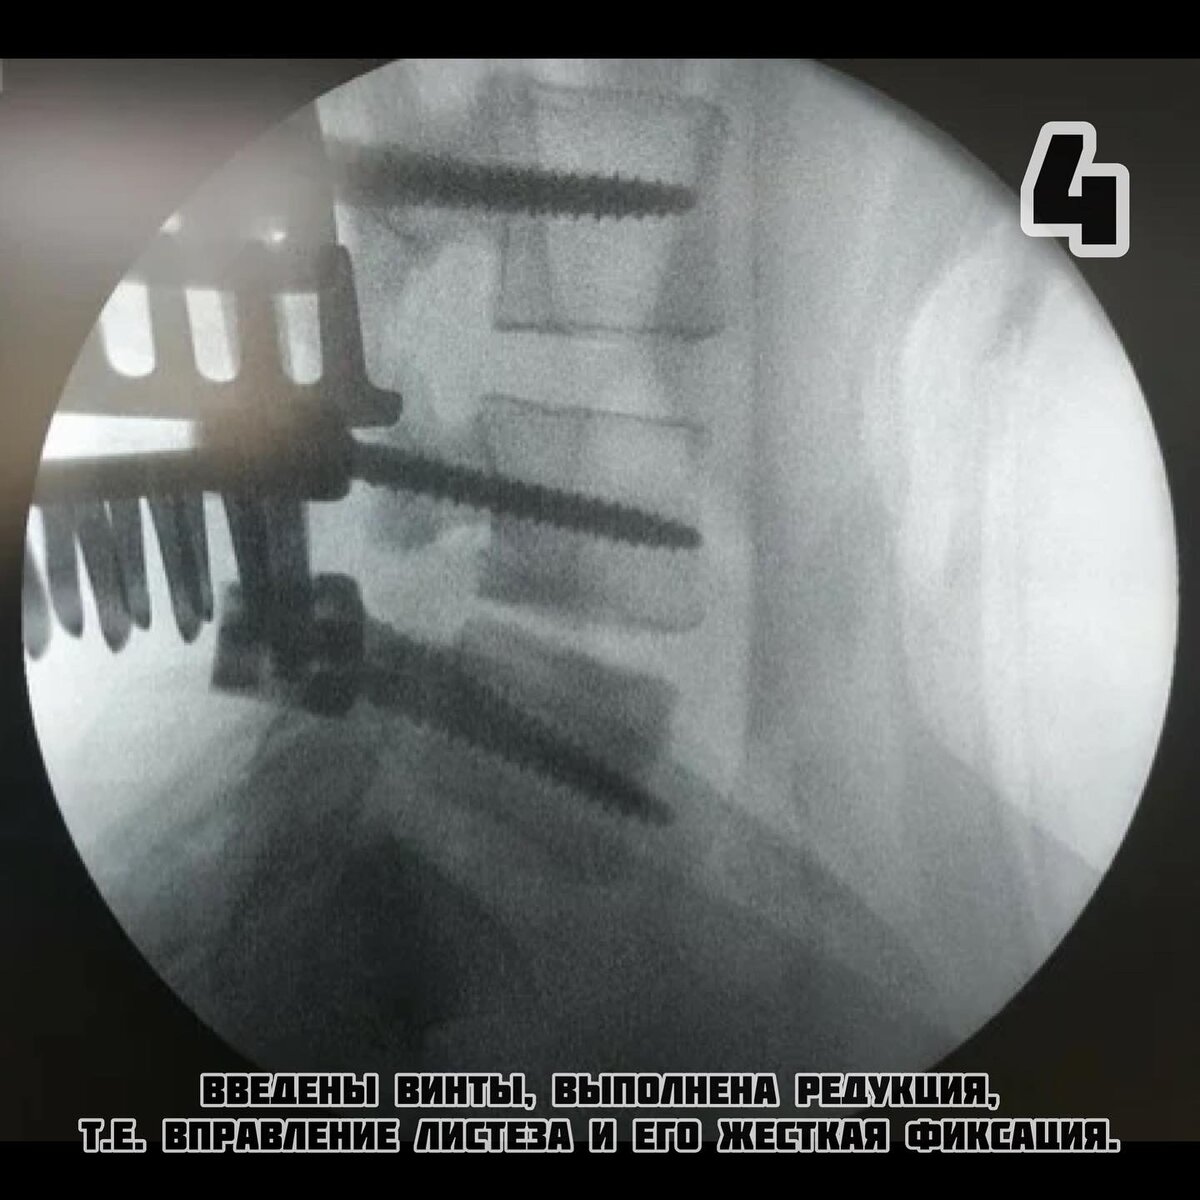

-4